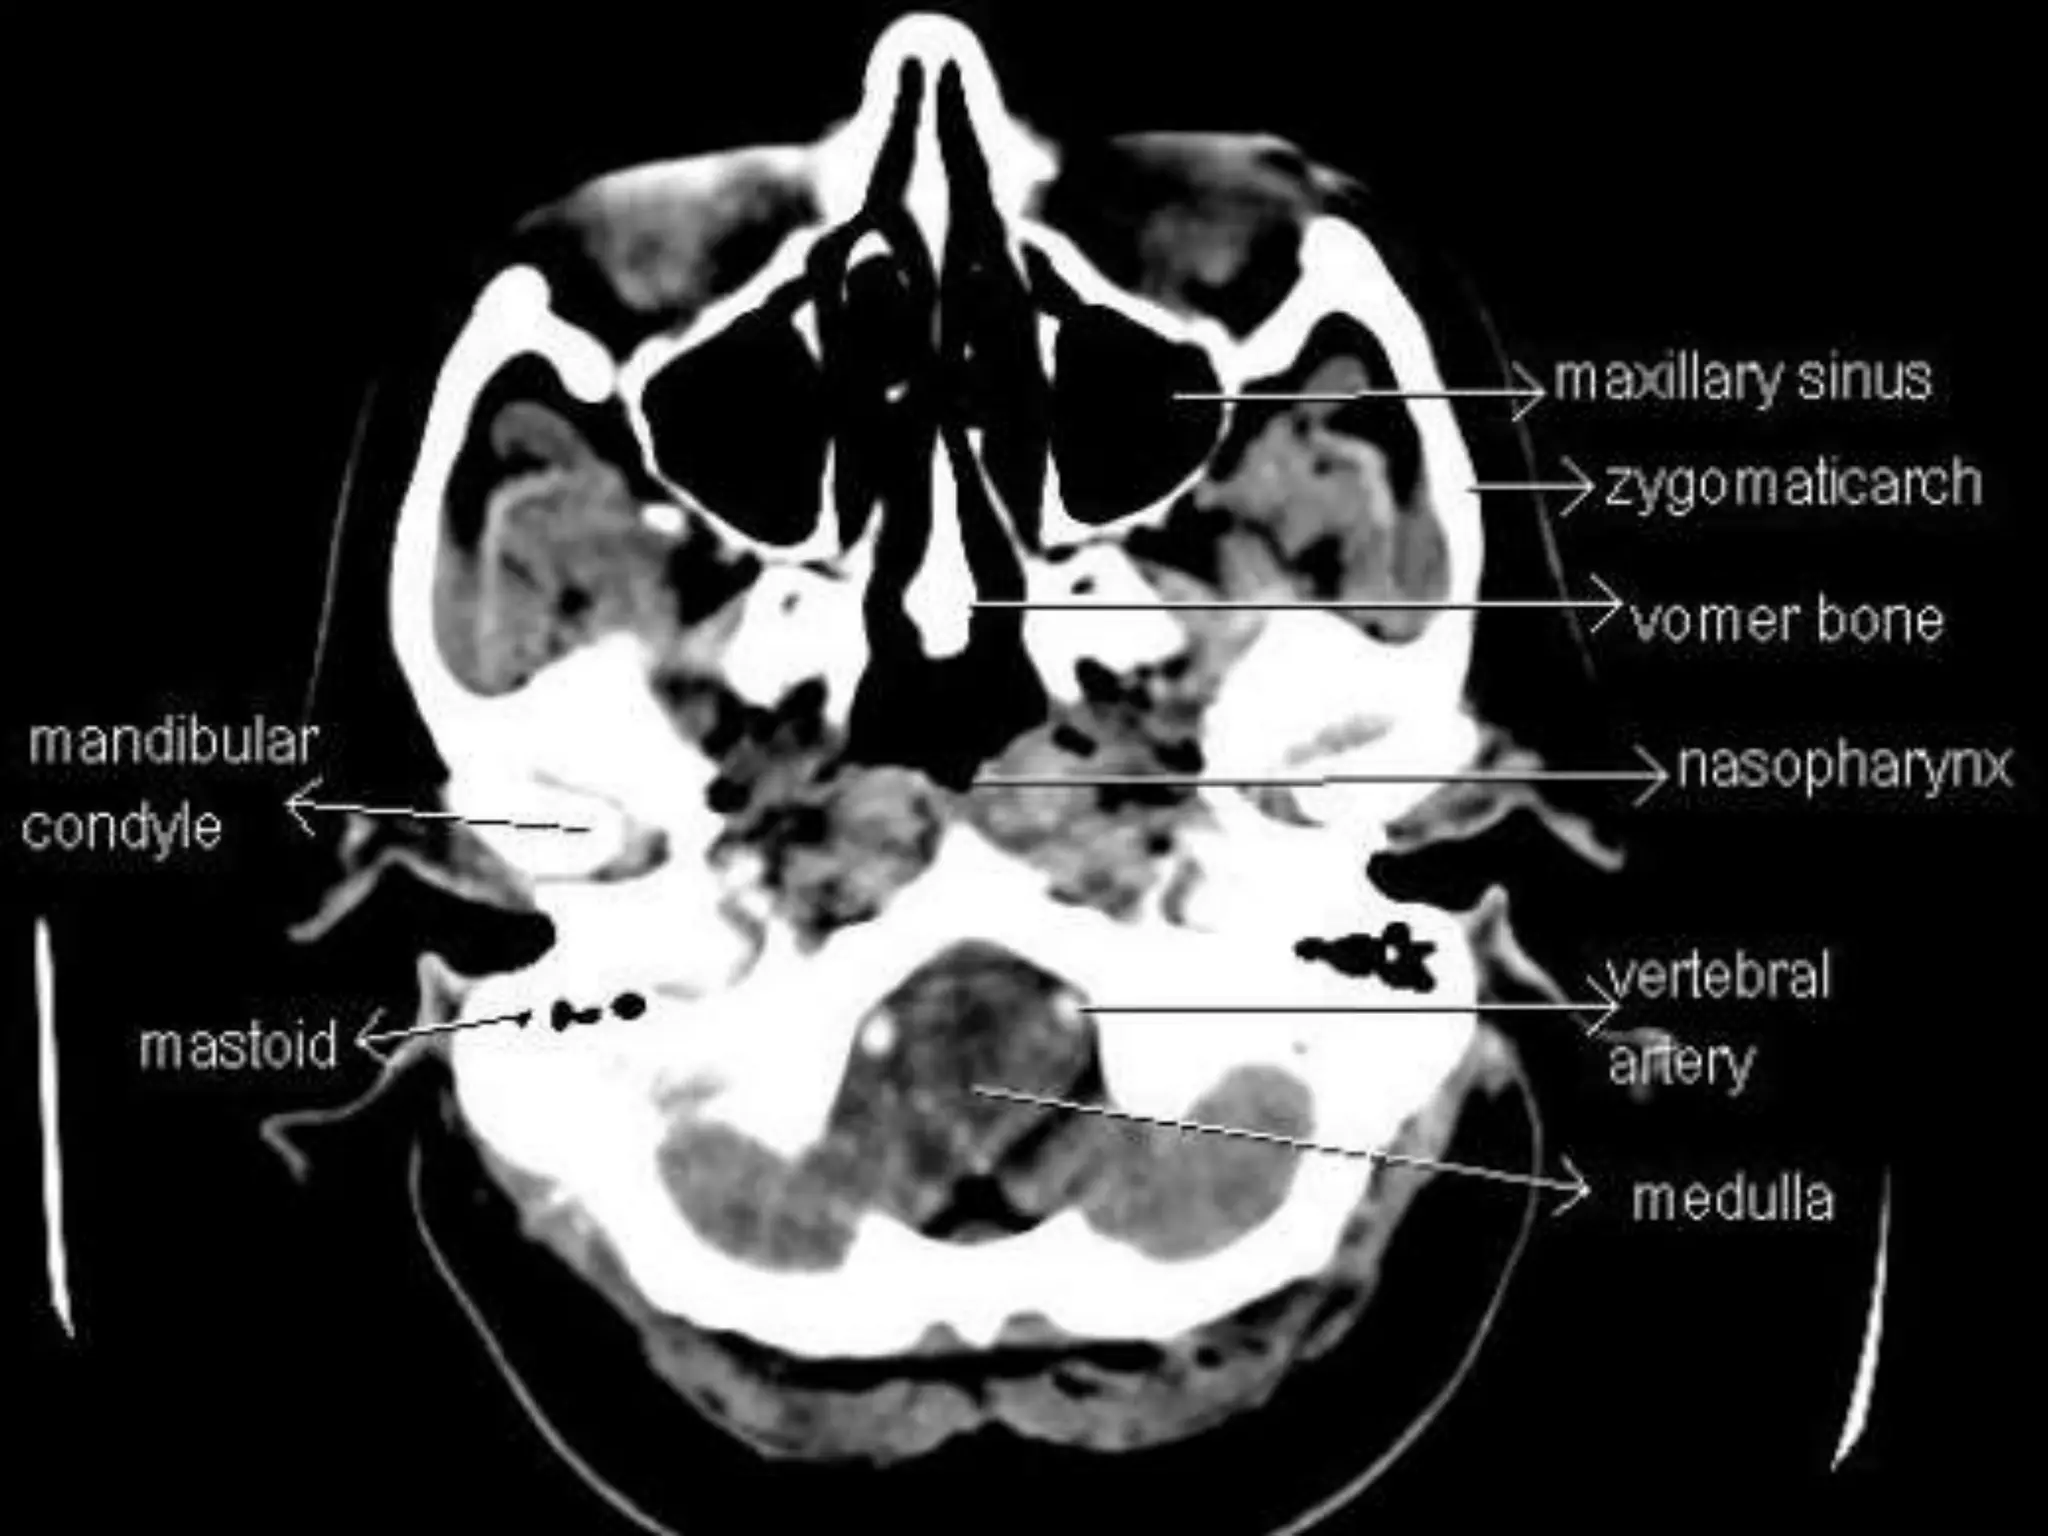

Sectional Anatomy: NormalAxial CT and MRI Anatomy. On CT and MR scans, the brain has been briefly viewed in infratentorial and supratentorial sections, as described below. CT scans are performed with a 15- to 20-degree angulation to the canthomeatal line at 8-mm increments. MRI scans are generally obtained parallel to the AC-PC line in the axial plane with 6-mm slice thickness. Using the sagittal view, the coronal sections are acquired parallel to the brain stem, and the sagittal sections are obtained perpendicular to the axial section. On MRI studies, cranial nerves IX and X can be demonstrated at this level because they emerge from the postolivary sulcus. The posterior aspect of the cerebellar hemispheres is outlined by the inferior portion of the cisterna magna.